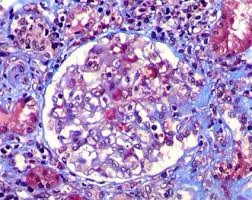

Este vídeo apresenta, de forma didática e baseada em evidências, os principais achados da tese de doutorado sobre amiloidose renal, com foco em proteômica glomerular e ativação do complemento. São discutidos aspectos diagnósticos, implicações fisiopatológicas e correlações clínico-patológicas relevantes para a prática do nefrologista. O conteúdo sintetiza dados inéditos de matriz extracelular glomerular e diferencia perfis entre subtipos de amiloidose. Trata-se de um material aprofundado e acessível, ideal para atualização de especialistas na área.